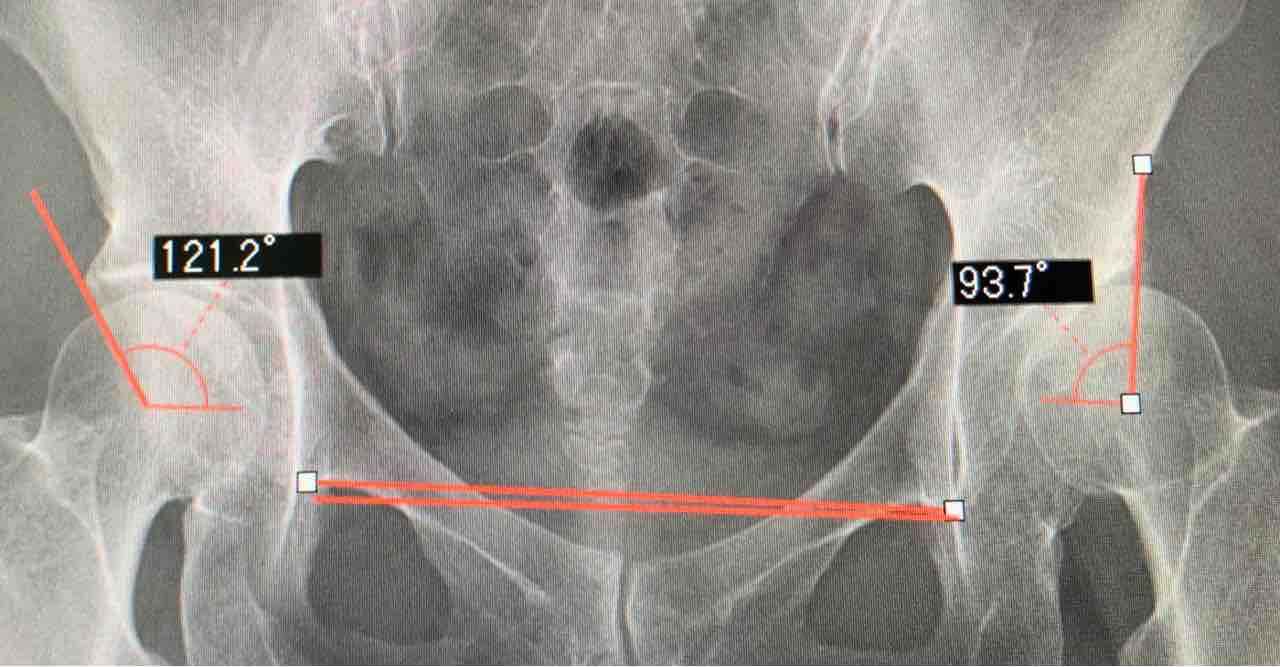

私の整形外科通いの話もして、

良さそうな病院だったから

おススメしておきました(^^)